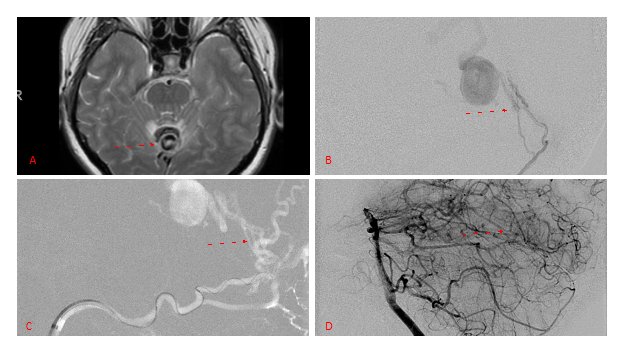

Figure 3. Right ECA AP and Lateral angiograms Pre (A and B) and Post NBCA embolization (C and D) Demonstrate near complete obliteration of right Occipital and Middle Meningeal Artery Fistulas

Figure 4. Left ECA AP and Lateral angiograms Pre (A and B) and Post NBCA embolization (C and D) Demonstrate near complete obliteration of Left Occipital Artery Fistulas.